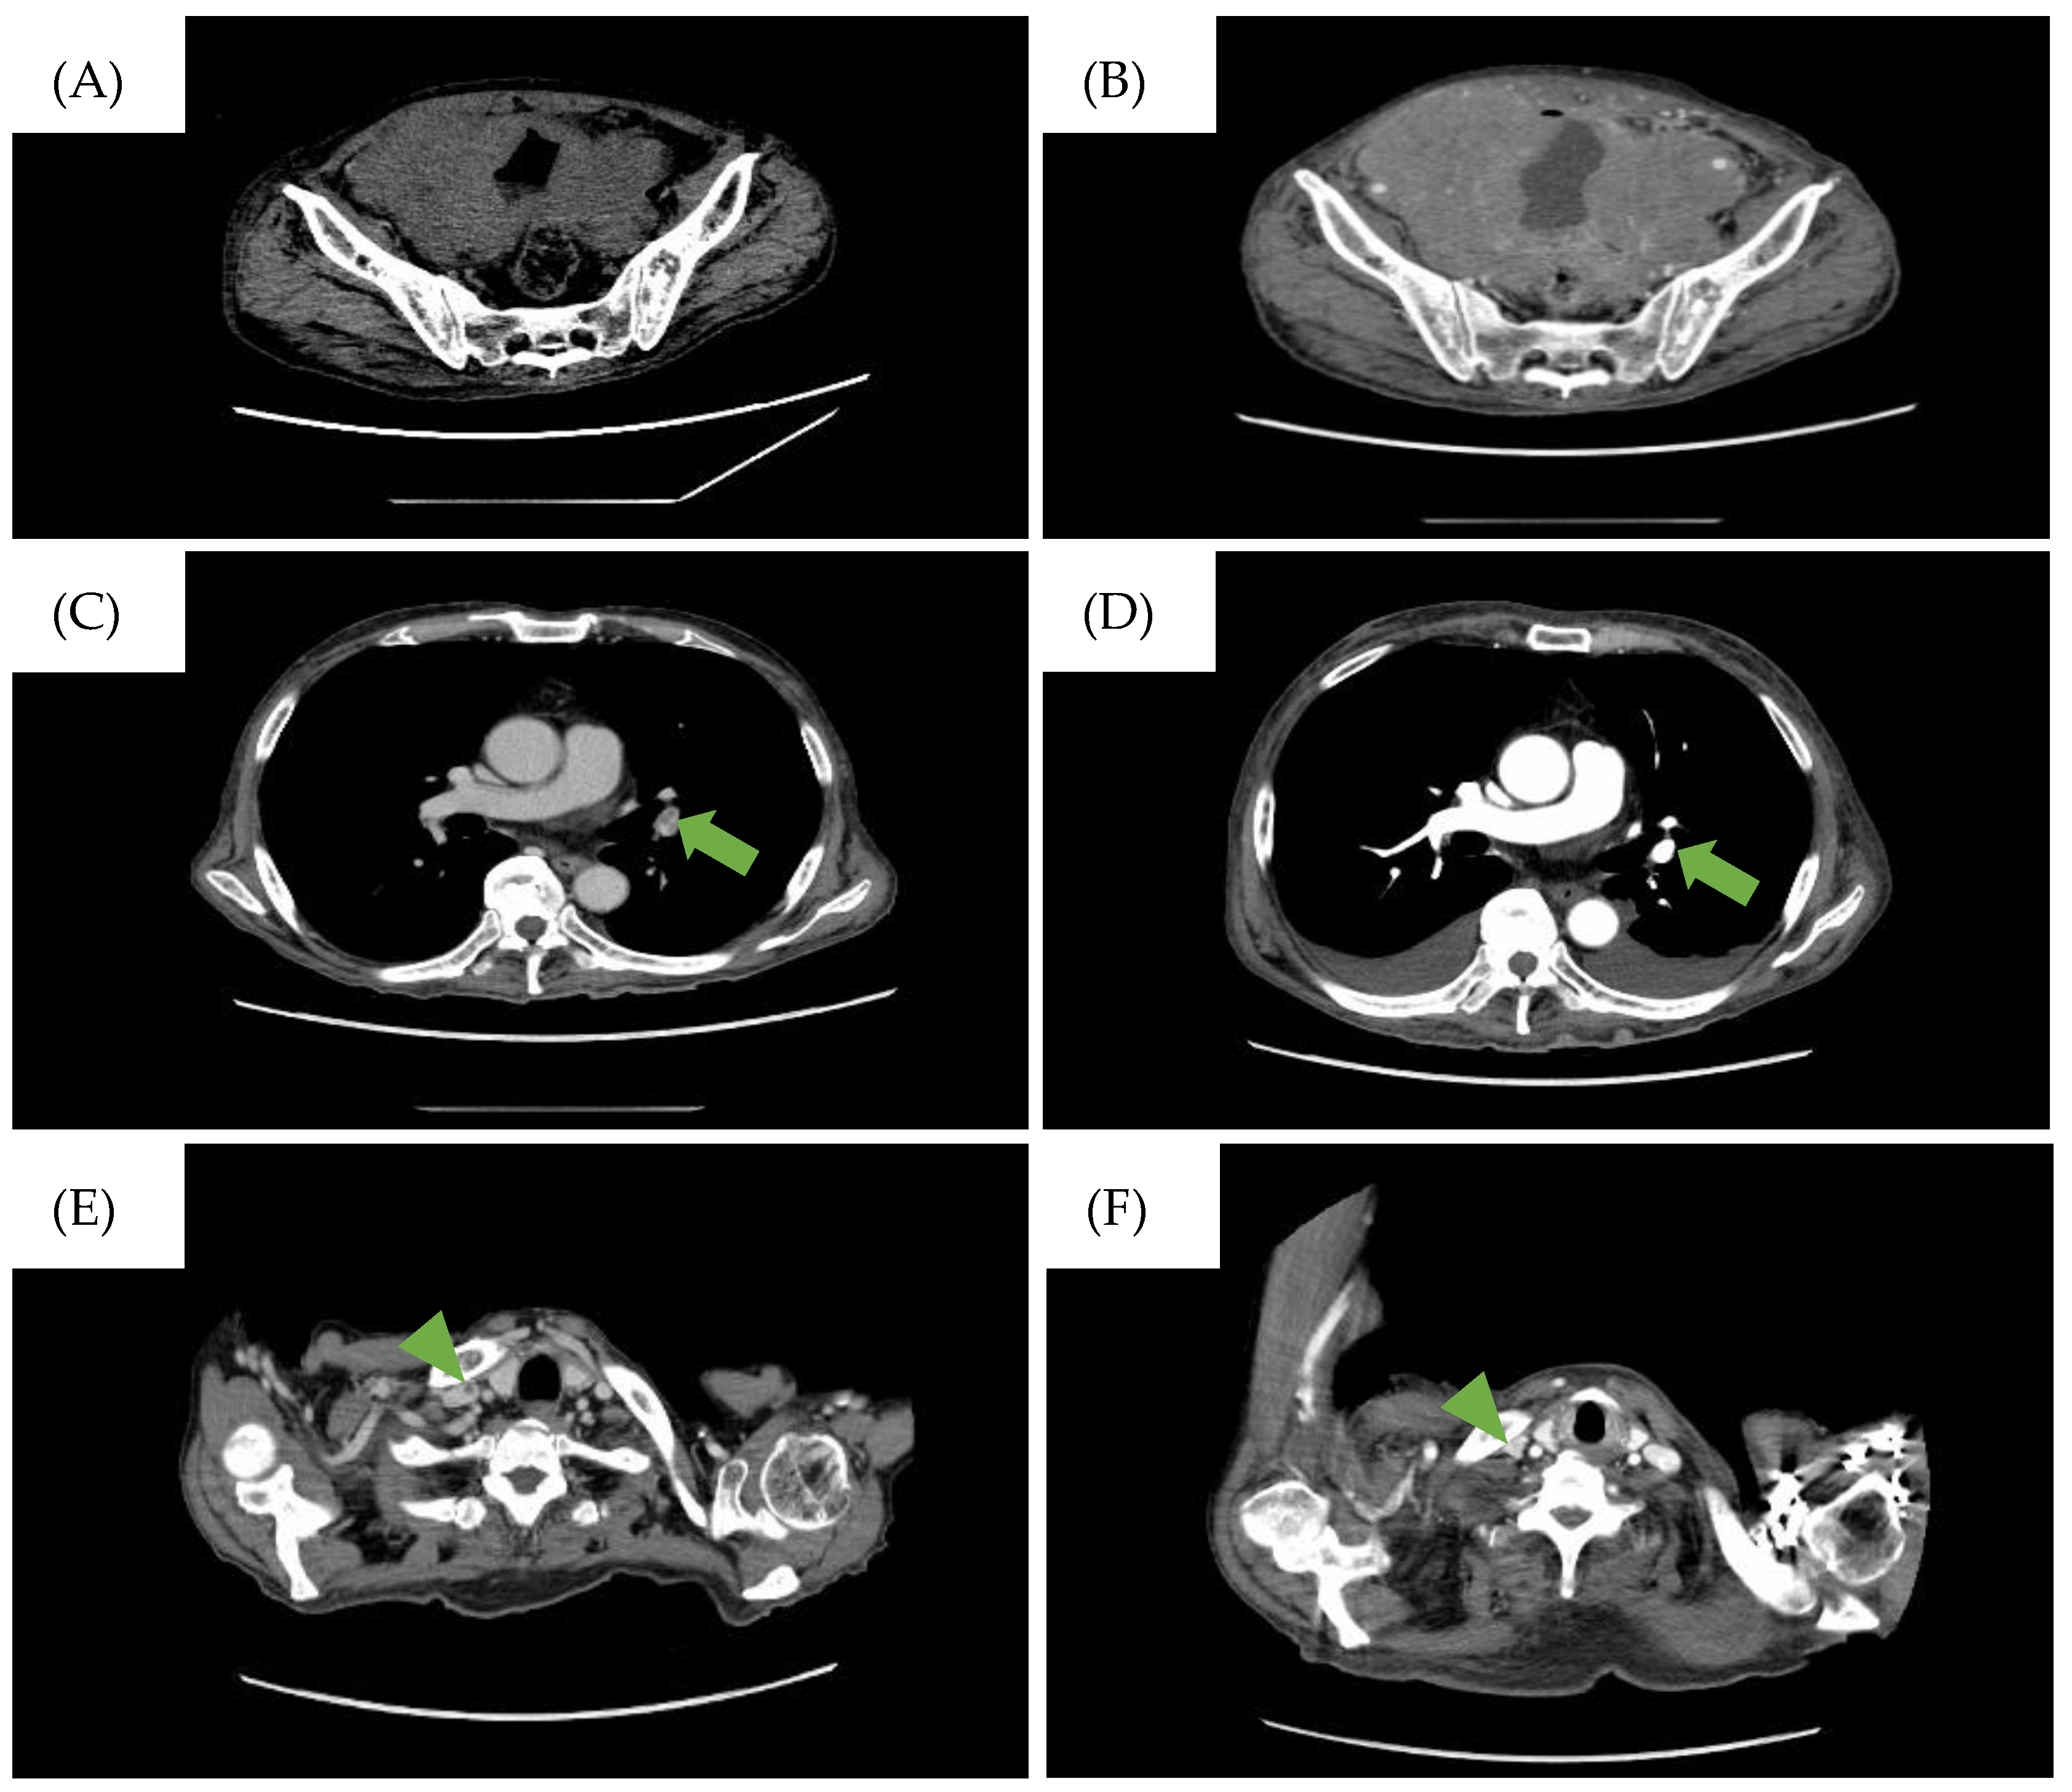

Figure 1.

CT findings during the clinical course of the patient. (A) CT scan on the day the patient was referred to our hospital. Diffuse bladder wall thickening up to 7 mm was observed. (B) CT scan taken when the patient complained of abdominal pressure. A large intra-abdominal mass was observed. The low-density area represents the pulmonary embolism (PE) in the (C) left pulmonary artery and (E) the right internal carotid artery and disappearance of the PE after treatment in the (D) left pulmonary artery (→) and (F) the right internal carotid artery (▶︎).

A 77-year-old man was referred to our hospital with fever, anorexia, and general malaise. Initial laboratory tests indicated severe renal failure, elevated levels of C-reactive protein and soluble interleukin-2 receptor, pyuria, and bacteremia due to Escherichia coli (Table 1). No malignant cells were confirmed from the urine cytology test. Computed tomography (CT) scans showed thickening of the bladder wall and increased opacity surrounding the bladder (Figure 1A), and pathological conditions such as trabeculation, malignant tumors, and infections including cystitis were cited as a differential diagnosis. However, he was diagnosed with sepsis associated with a severe urinary tract infection due to the laboratory findings mentioned above. Treatment for an infection by antibiotics and hemodialysis for uremia were carried out. His renal function and general condition improved after these treatments, leading to his discharge one month after admission.

However, the patient returned a week later, reporting abdominal pressure. Follow-up CT scans revealed a large intra-abdominal mass attached to the bladder wall (Figure 1B), and deep venous thrombosis (DVT) in the bilateral lower extremities, pulmonary embolism (PE) in the left pulmonary artery, and arterial thrombosis of the right internal carotid artery were also identified (Figure 1C). These thromboses were likely due to compression of the bilateral internal iliac veins by the tumor and tumor-induced coagulation abnormalities. A CT-guided biopsy of the mass confirmed this, and pathological findings showed diffuse infiltration of large, atypical cells with CD20-, CD10-, and BCL6-positive and CD3-, c-MYC-, BCL2-negative immunostaining. The Ki-67 index was 90% in these specimens (Figure 2). Therefore, the diagnosis of DLBCL was made. Further imaging studies showed no lymphadenopathy, and bone marrow infiltration tests were negative, establishing a diagnosis of primary bladder DLBCL, stage IE (bulky) according to the Ann Arbor classification [8], a favorable Revised International Prognostic Index (calculated by age, lactate dehydrogenase levels, performance status, Ann Arbor staging, and number of extra nodal lesions; evaluated as 0 points: good, 1–2 points: favorable, 3 points or more: poor) due to age and high lactate dehydrogenase levels, and germinal center B-cell subtype (CD10-positive).

Treatment with R-CHOP regimen (rituximab, cyclophosphamide, doxorubicin, vincristine, and prednisone) was initiated alongside warfarin and heparinization due to thrombosis risk. After one cycle of R-CHOP, a partial response was observed, and the PE resolved (Figure 1D). However, after three cycles (three months after cycle one started), the patient experienced severe desaturation and a massive pleural effusion was detected on a CT scan. Large lymphocytes with constriction in the nucleus and a distinct nucleolus were found in the thoracentesis sample and confirmed a DLBCL relapse. Given the patient’s limited physical condition and preferences, invasive treatments were halted in favor of best supportive care.